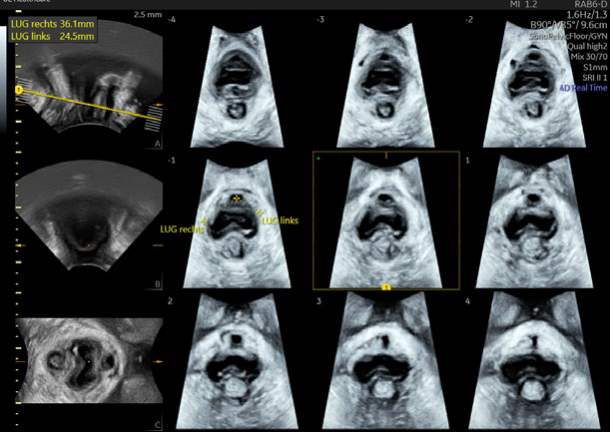

• SonoAVCTM & Auto Caliper measurements for follicles

• AI based functionality with fetalHS, SonoCNS, SonoPelvicFloor 2.0

• SonoGYN with Fibroid Mapping